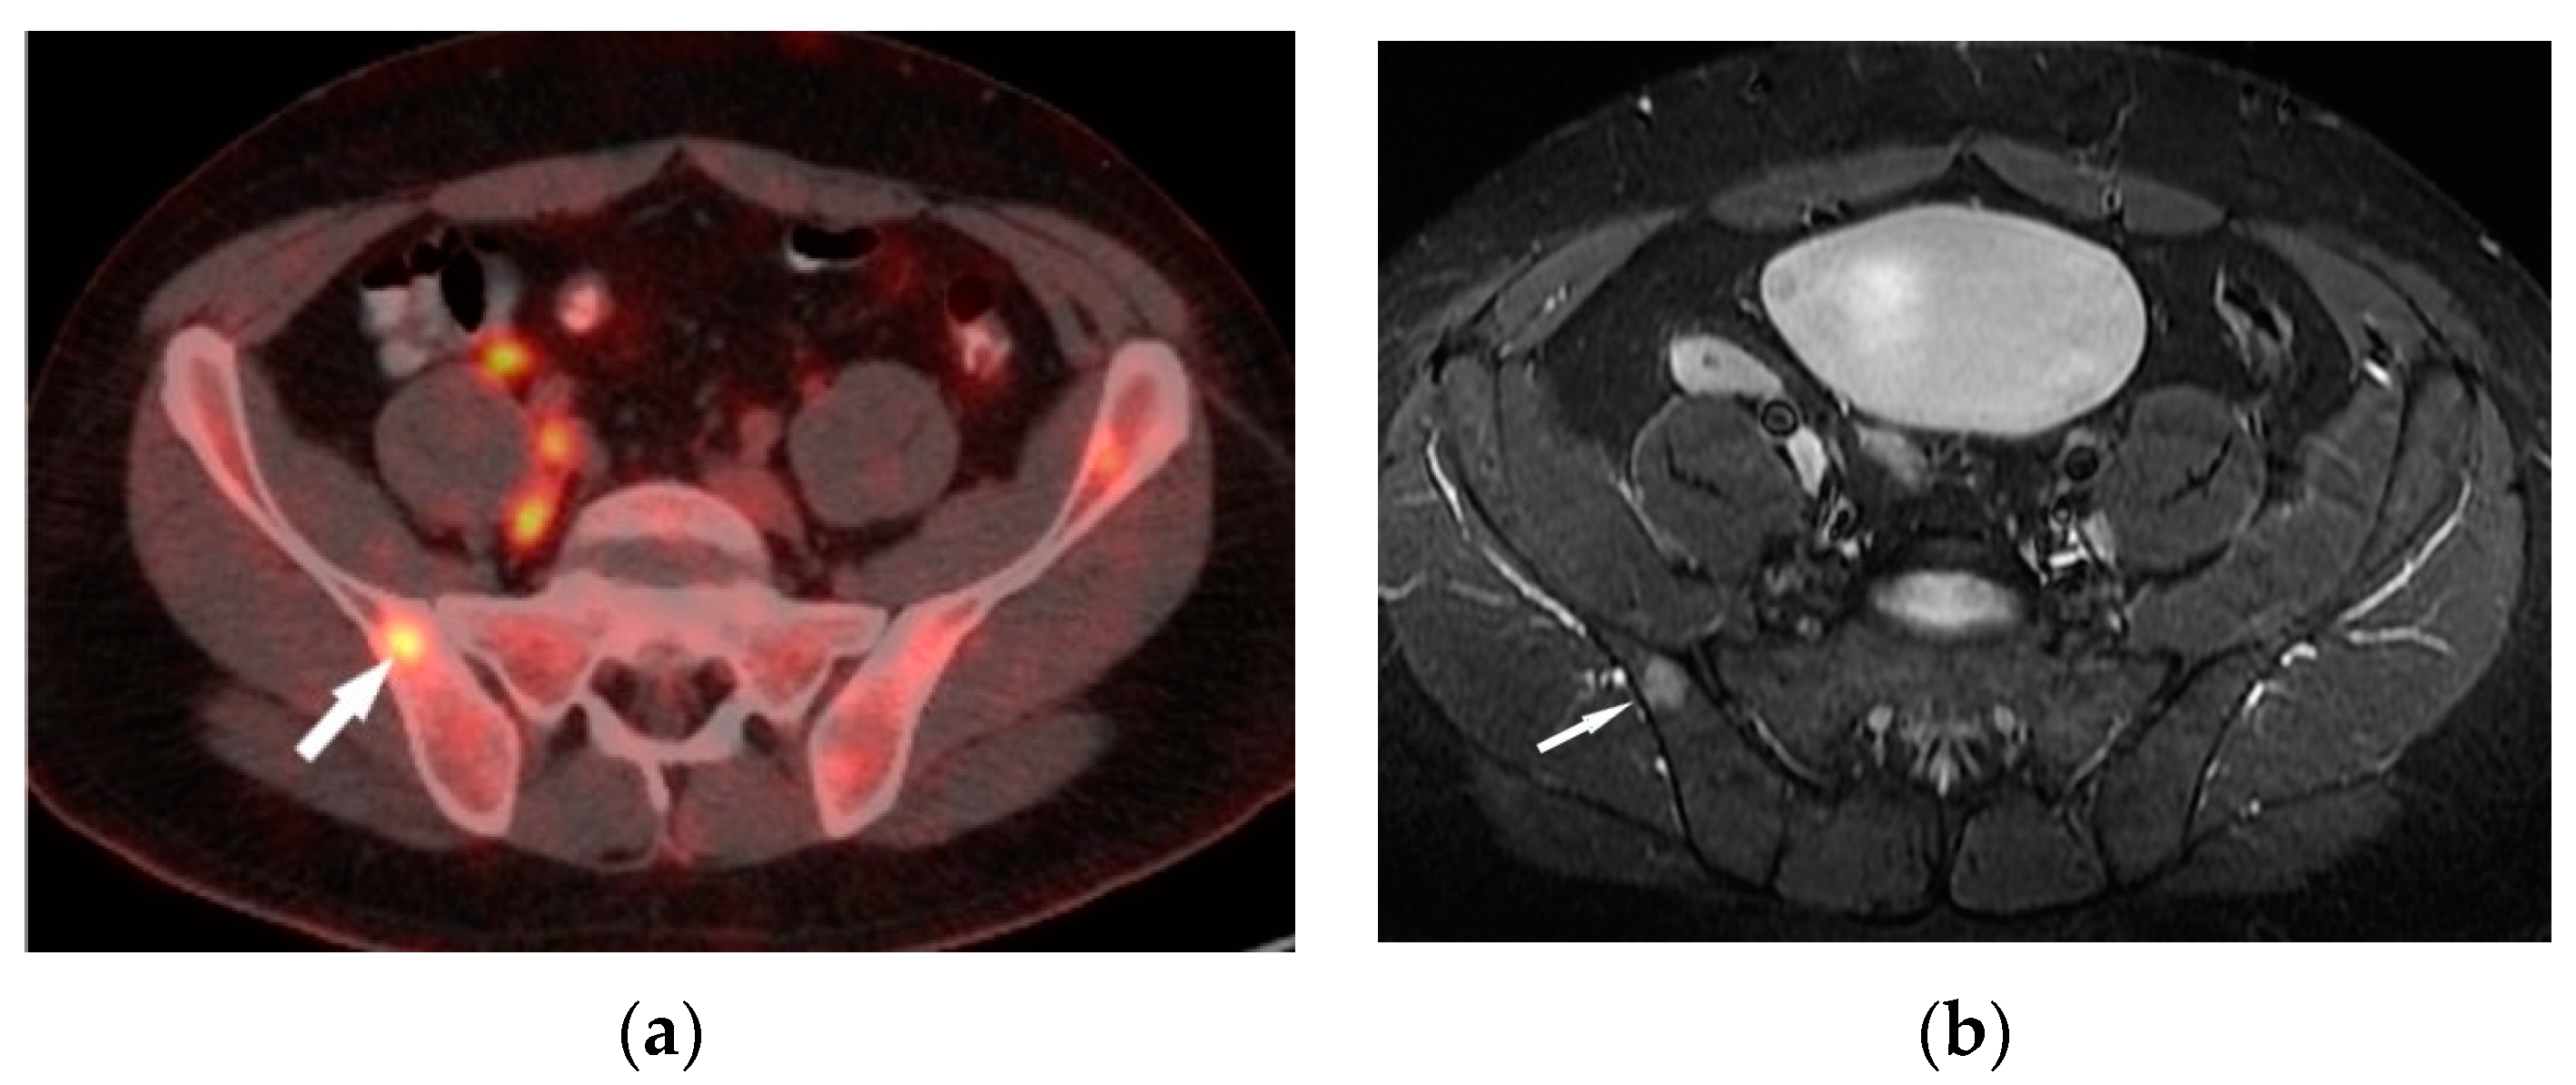

Figure 4. FDG-PET/CT (a) and T1–weighted MRI image with contrast enhancement (b) presents an enhanced lesion with increased FDG uptake (white arrows) in the right iliac bone.

A decrease in the FDG uptake in the follow-up PET/CT study is indicative of a metabolic response associated with regression of the sarcoid foci. A promising diagnostic tool for musculoskeletal sarcoidosis appears to be a hybrid of PET and MRI [16] (Figure 4a,b).